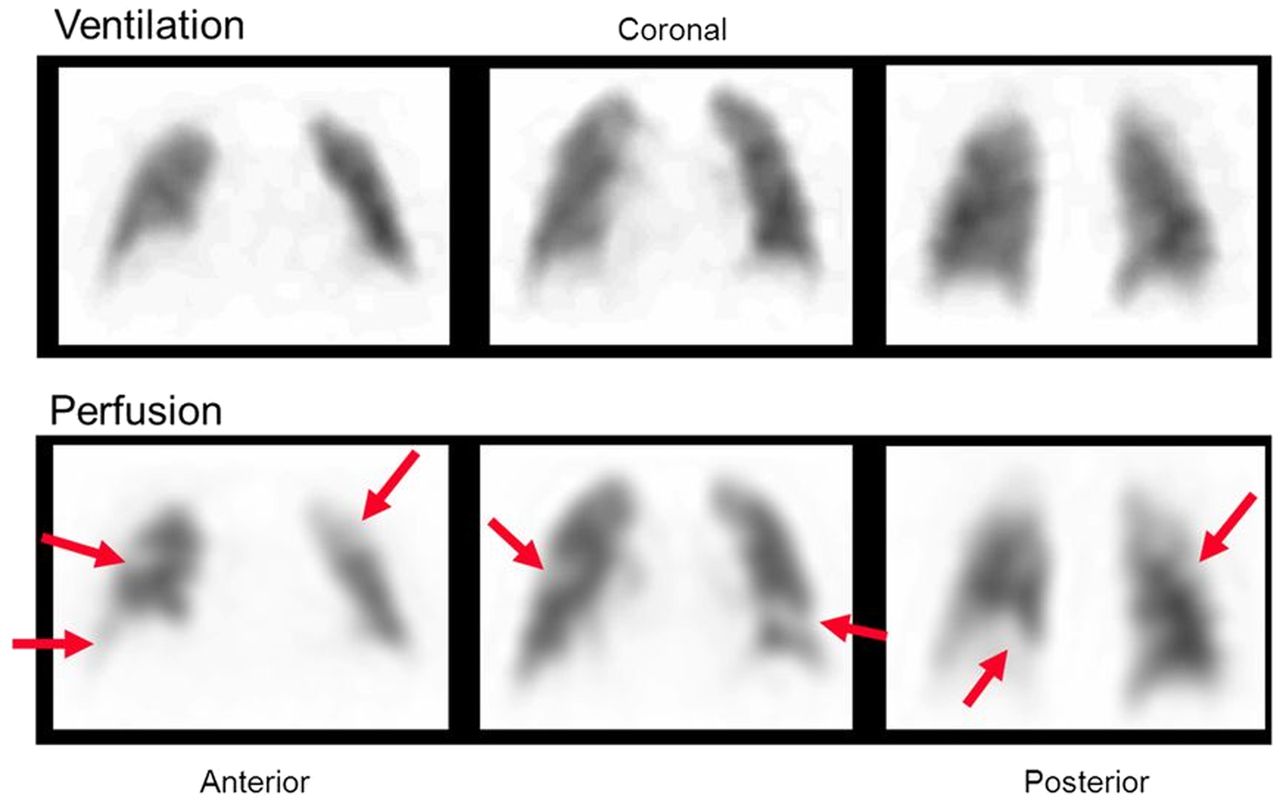

Lung Ventilation Perfusion (V/Q) Scan indications Nuc Med

Indication: Pulmonary Embolism

Lung Ventilation Perfusion scan Nuc Med vs CTPA

Lung (V/Q) Advantages:

Contrast allergy

Less ionising for pregnant patients

Can image those with renal impairments

Pharmaceuticals used in Lung (V/Q) scans

Ventilation= 99mTc Technegas

Perfusion= 99mTc MAA

PE Appearance in Lung (V/Q) scan

Normal ventilation, perfusion defect (mismatch)

Poor image quality causes for Lung V/Q scan

COPD= poor ventilation distribution